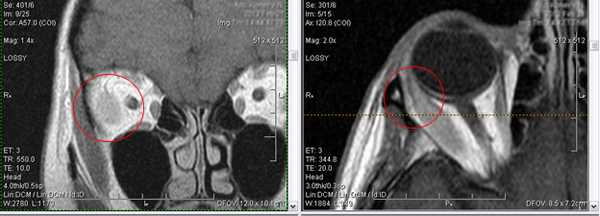

Нарушения зрения развиваются медленно или стремительно. Длительное медленно прогрессирующее развитие нарушений зрения характерно для близорукости и дальнозоркости, а резкое - для нарушения проходимости центральной артерии сетчатки, гемофтальма, приступа глаукомы. Внезапные нарушения зрения зачастую оказываются необратимыми, поэтому требуют обязательной доскональной диагностики и срочного вмешательства. Рассмотрим на примере, как визуализируются изменения орбит при МРТ-диагностике.

4. Дакриоаденит.

Это острое, либо хроническое заболевание слезной железы воспалительного характера. Инфекции чаще приводят к острому дакриоадениту. Лимфолейкозы и алейкемические лимфаденозы, туберкулезная и, реже, сифилитическая инфекции могут вызывать хронический дакриоаденит.